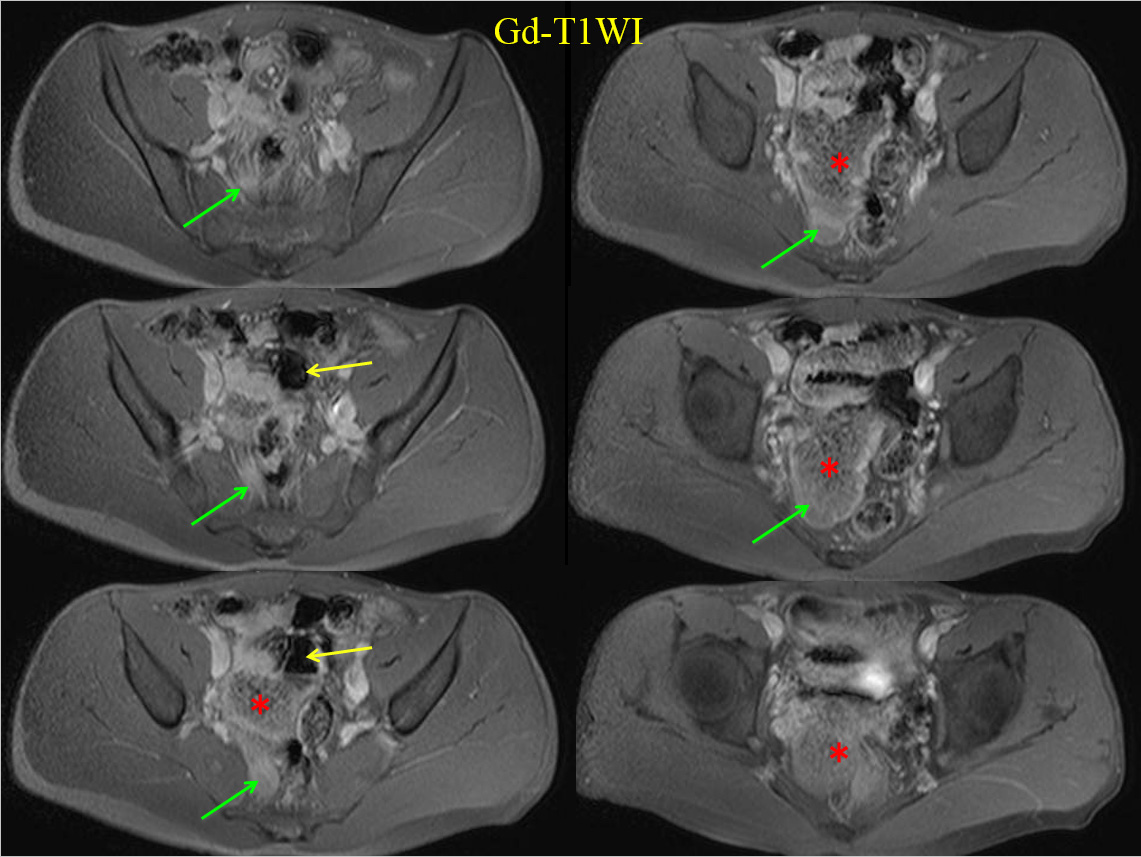

• Gd-T1WI

MRでは、骨盤内に大きな嚢胞性病変を認める。

すなわちT2WI、T1WIでいずれも高進号を呈すが、脂肪抑制で抑制されず、造影で辺縁部のみわずかに濃染される。

内部には不均一で貯留物があると認識されるが、血性を示唆する所見には乏しい。

骨盤内の嚢胞性病変の鑑別となるが、男性であるため卵巣由来は否定的である。水平断像および冠状断像を丹念に読影すると、同病変は小腸と連続しており、腸管構造の一部であることがわかる。病変の局在は回腸末端に近く、年齢、経過を加味すると、メッケル憩室が最も考えられる。